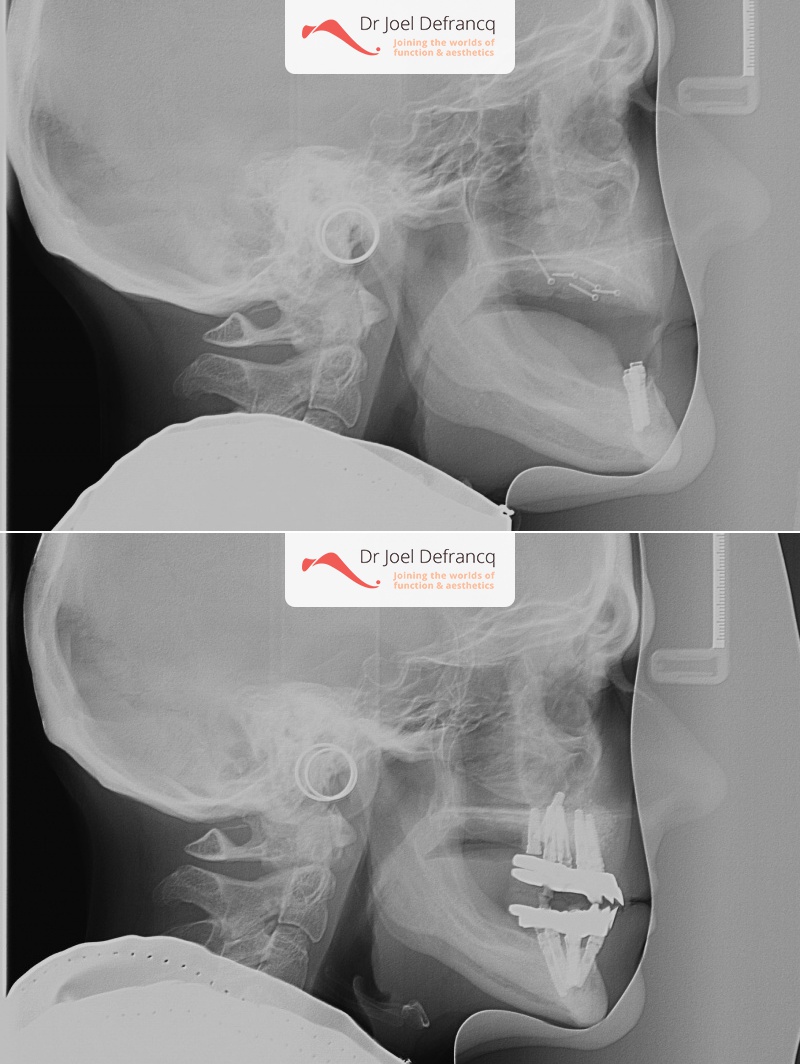

Dentale diagnose

- Klasse I

Behandeling tandheelkundige implantaten

- Vaste tanden op implantaten (bovenkaak)

- Vaste tanden op implantaten (onderkaak)

- Implantaten met beenopbouw